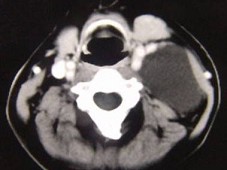

女性,30岁,右侧腮腺无痛性包块5个月,无面瘫,触诊肿块质韧,表面光滑。大小约6×8厘米,B超示腮腺浅叶实性肿块 ,均质,包膜完整。患者相片及影像资料见下图。

8.患者应该诊断为  (    )

9.患者的最佳手术方式是  (    )

10.手术中若以下颌缘支寻找面神经主干,其主要标志是  (    )

正确答案:8.B;9.B;10.A